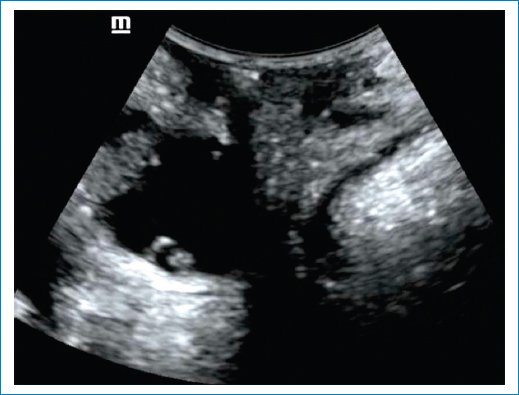

• – Útero y el cuello uterino: podemos evaluar el descenso del útero vs. elongación del cuello uterino. Se evalúa el descenso del útero con respecto a la sínfisis del pubis y se toma de referencia el cuello uterino o el fondo de saco de Douglas en caso de histerectomía. Prolapso: 15 mm por debajo de la línea de la sínfisis del pubis (Fig. 14).

Figura 14. Se observa el cuello uterino que ocupa la cavidad vaginal.